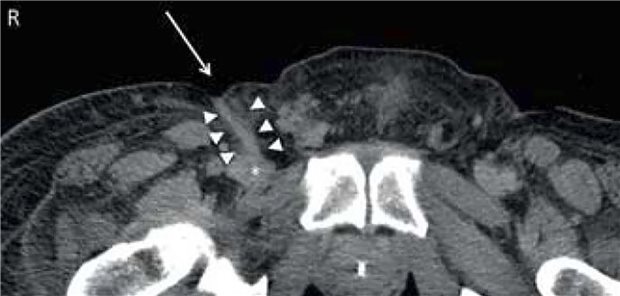

Hinter akuten Nackenschmerzen bei älteren Menschen könnte auch das Crowned-Dens-Syndrom (CDS) stecken. Es ist selten, was zu Fehldiagnosen führen kann. Ein Fallbericht zeigt, woran man es erkennt.